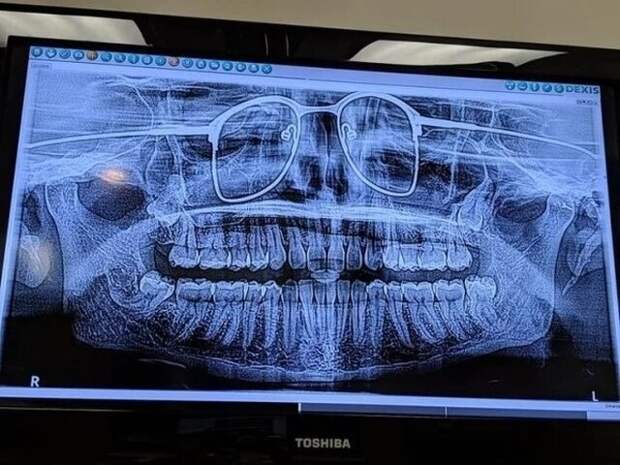

Мозг человека в коме и мозг здорового человека  Панорамный снимок лицевого черепа

Панорамный снимок лицевого черепа  16-месячный мальчик проглотил Спанч Боба